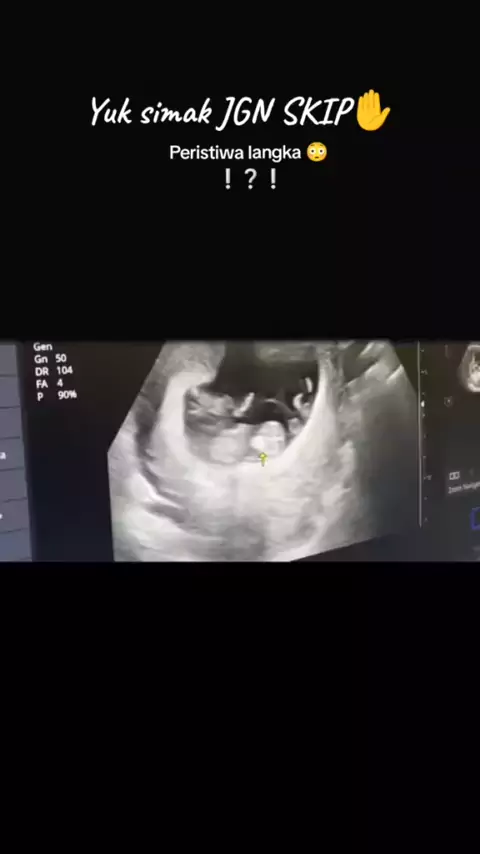

#ikhtiarpejuangpromil#garisdua#pejuanggarisdua